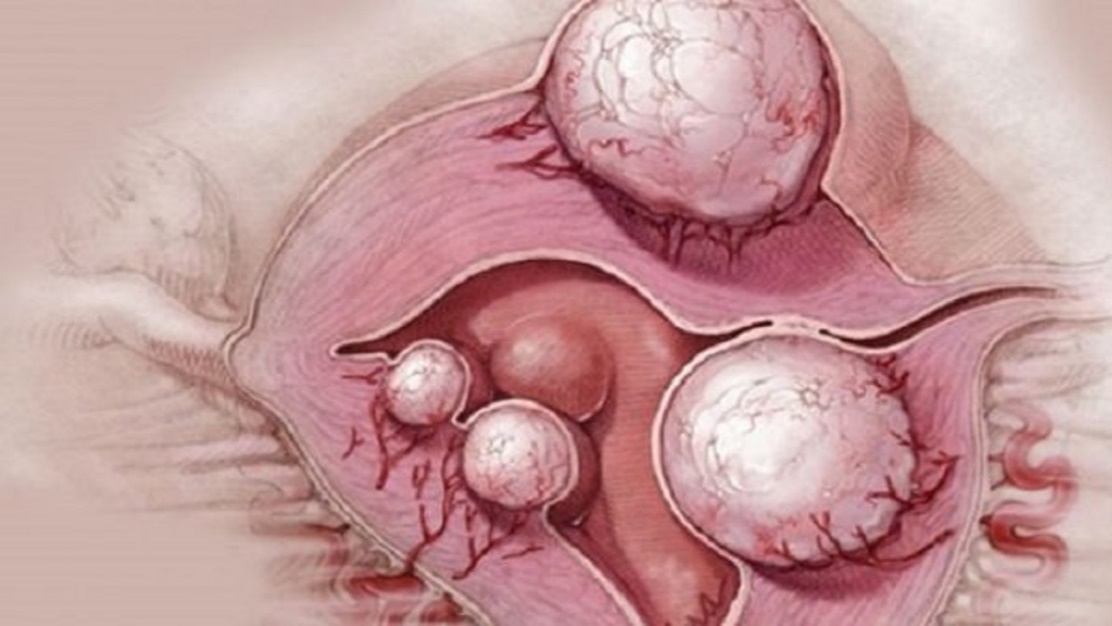

Гистологические изображения фолликулярной кисты яичника